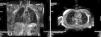

Results and conclusionsThe ultrasound sequence to perform this block is shown, together with simple X-ray dye images and gadolinium MRI images to understand the spread and pathways that can explain the benefit of this novel approach.

Resultados y conclusionesMostraremos la secuencia ecográfica para poder realizar este bloqueo junto con imágenes con contraste radiográfico y resonancia magnética con gadolinium para poder entender los beneficios de este bloqueo.